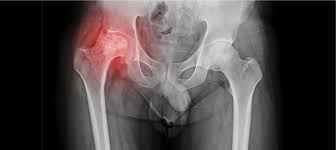

At Varunam Hospital, we specialize in the diagnosis and treatment of Avascular Necrosis (AVN), a condition that occurs when blood supply to the bone is disrupted, leading to bone tissue death. Our dedicated team of orthopedic specialists in Chandrapur is committed to providing comprehensive care tailored to each patient’s needs.

We utilize advanced imaging techniques to accurately diagnose AVN and assess the extent of the condition. Treatment options range from non-invasive methods such as medications and physiotherapy to surgical interventions like core decompression and joint replacement, depending on the severity of the disease.